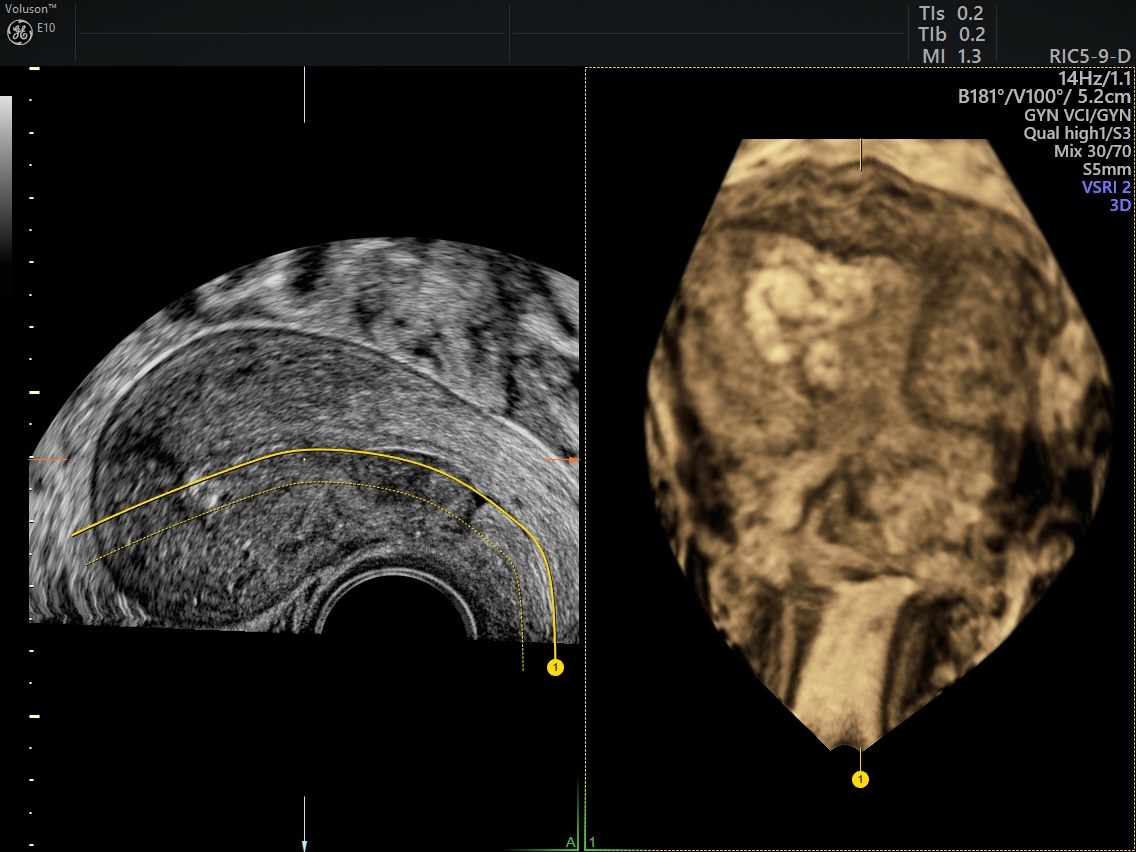

From www.volusonclub.net

How Retained Products of Conception Can Impact Fertility Empowered Women's Health What Do Retained Products Of Conception Look Like Should consider abnormal if heavy or last >3 weeks. Retained products of conception (rpoc) generally result after first half of pregnancy termination and also may occur after vaginal or cesarean. Retained products of conception (rpoc) refer to the persistence of placental and/or fetal tissue in the uterus following delivery, termination of pregnancy or a miscarriage. Retained products of conception (pocs). What Do Retained Products Of Conception Look Like.